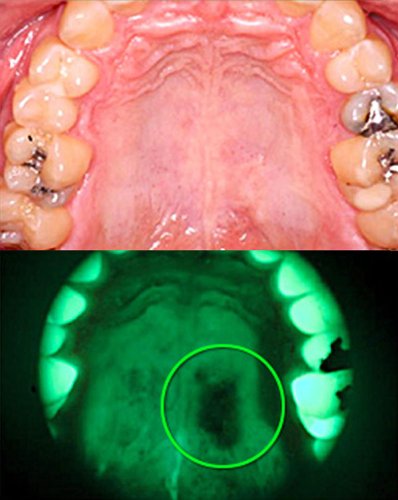

VELScope VELScope

Szájüregi rákszűrés Szájüregi rákszűrés

Gyanús elváltozás Gyanús elváltozás

A VELscope rendszer biztonságos, látható kék fényt bocsát ki, amely gerjeszti a nyálkahártya szöveteit és fluoreszkál. A fogorvos megvizsgálhatja a lágy szöveteket és azonosíthatja a gyanús elváltozásokat. Az egészséges szövetek jellemzően élénkzöld fényként jelennek meg, míg a gyanús elváltozások a fluoreszcencia hiányát okozzák, és sötét színűnek tűnnek.